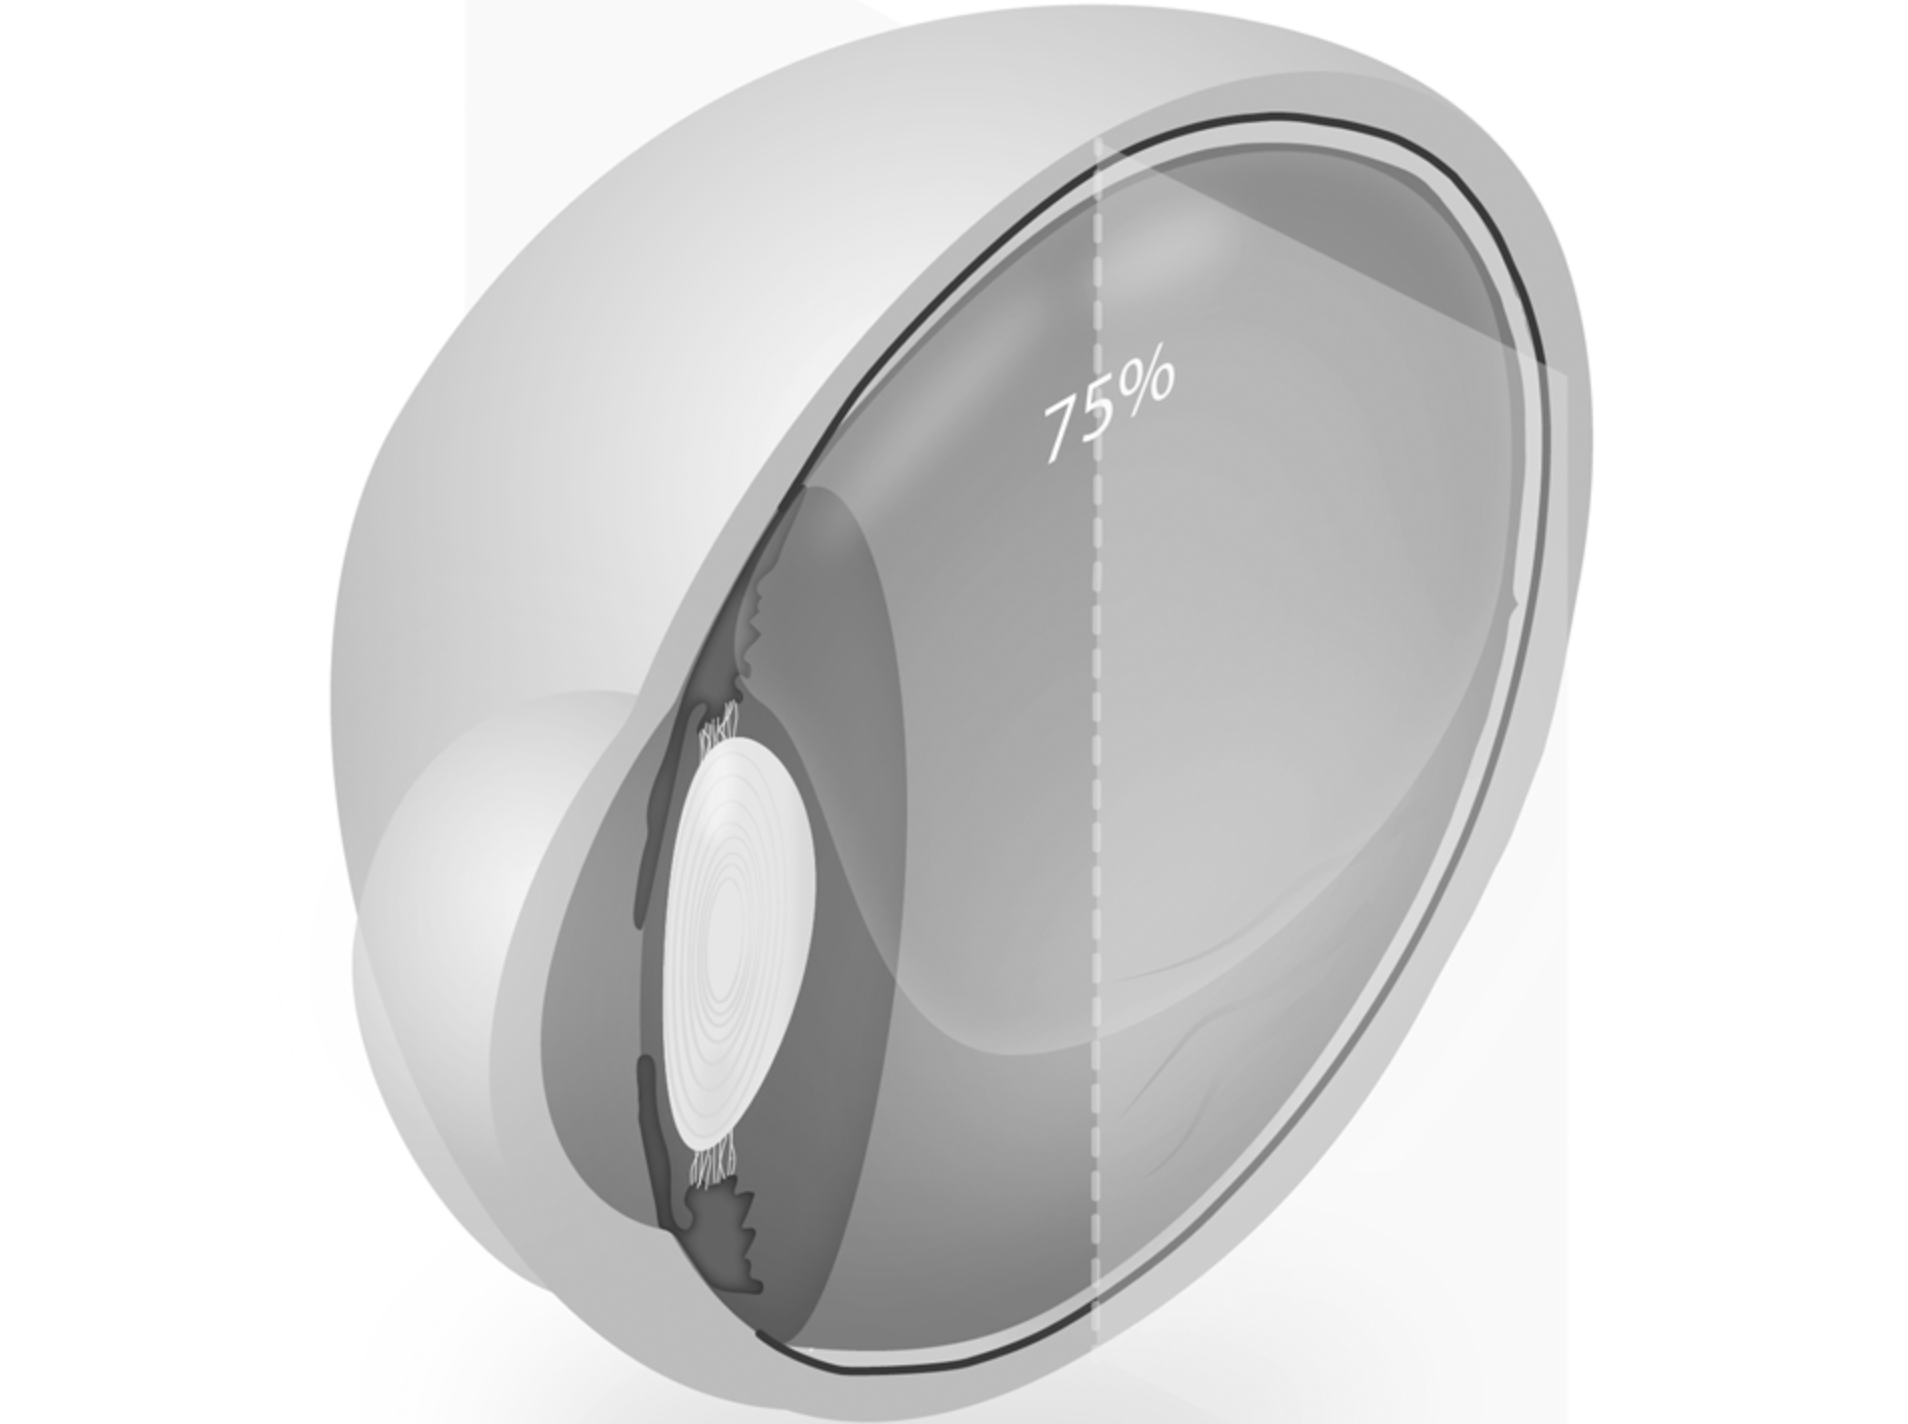

Visual Acuity Prediction

The framework is combined with a deep learning approach to automatically predict visual acuity outcomes for people undergoing surgery for idiopathic full-thickness macular holes using 3D spectral-domain optical coherence tomography images. To overcome the impact of high variation in real-world image quality on the robustness of DL models, comprehensive imaging data pre-processing, quality assurance, and anomaly detection procedures were utilised.

Vitreo-Retinal Surgery

The NHS became the first national health system pledging to attain 'net zero' emissions, a target it aims to achieve by 2040. Ophthalmologists have a role in making changes to mitigate our carbon footprint by considering a use of fluorinated gases ('F-gases').